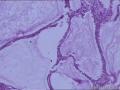

宫颈环切腺体有问题吗

性别年龄45临床诊断

一般病史白带量多十余年,接触性出血半年

标本名称宫颈环切标本

见两巢这样的腺体

慢性宫颈炎潴留性囊肿形成

慢性宫颈炎。